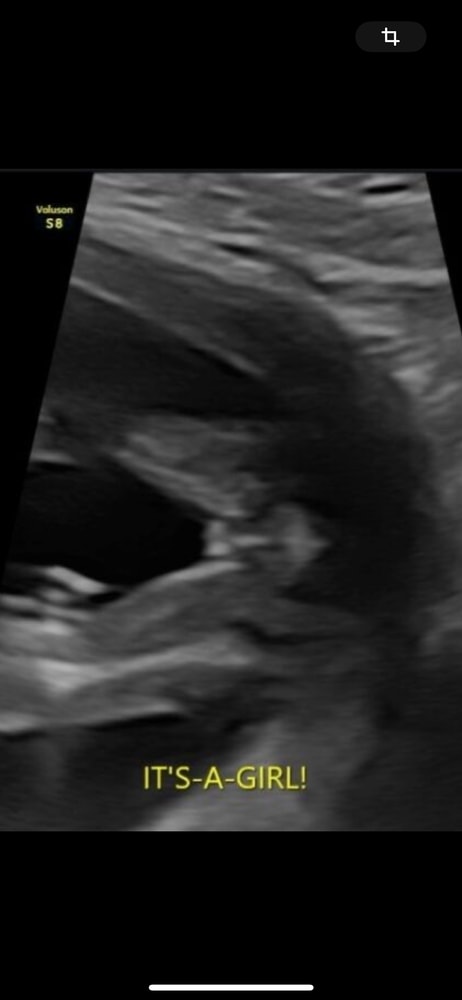

Вот вид снизу у девочки, срок 15 недель.

Анастасия, ого😍🥹я бы подумала что это писюн пацана если честно 😅Наверное все таки реально кто как видит .Спасибо за фото узи🤍

Жужу, да ну, явно же видно "кофейное зернышко". А вот на вашем снимке вижу прям мошонку)